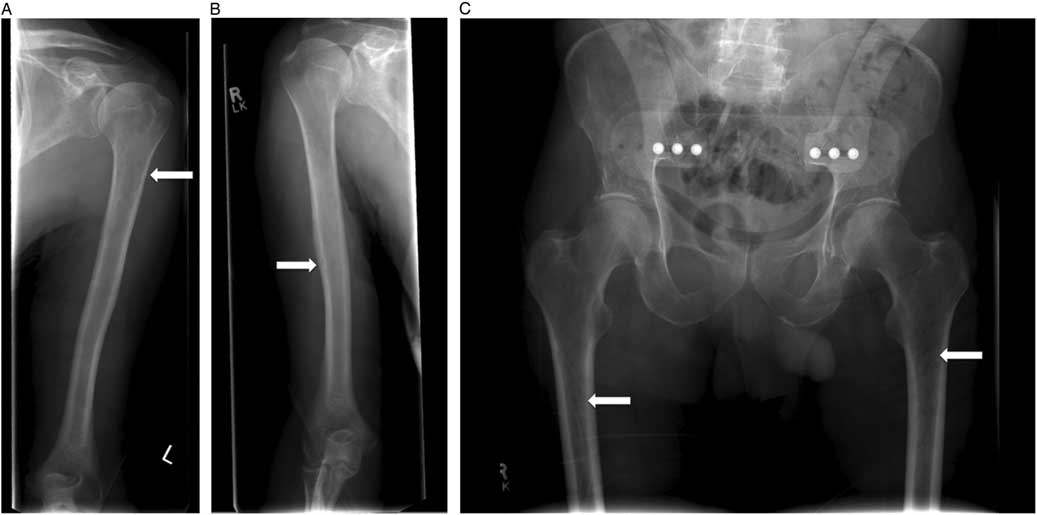

Laboratory investigations revealed pancytopenia, with a hemoglobin of 115 (range 137–180) g/L, leukocyte count of 1.9 (range 4.0–11.0×109)/L, and a platelet count of 135 (range 150–400×109)/L. Red blood cells were normocytic with a low reticulocyte count of 1%, and his peripheral blood smear demonstrated rouleaux cell formations. His serum electrolytes and creatinine were within normal limits. Hypercalcemia was detected with a corrected calcium level of 2.80 (range 2.10–2.55) mmol/L. New thoracic and lumbar spinal radiographs revealed subacute compression fractures involving the T11, L1, L2, and L3 vertebrae that were not present on the original films ordered by the family physician (Figure 2).

Figure 2 Lumbar spine radiograph acquired on presentation to the emergency department at 14 days following the initial spinal imaging. Loss of vertebral height of L1 (32%) and L2 (34%) as well as a mild central compression of L3 are revealed.

This patient was admitted and received further investigations to elucidate the cause of his compression fractures, pancytopenia, and hypercalcemia. The serum protein electrophoresis revealed an elevated gamma globulin, and urine protein electrophoresis revealed free lambda light chains. Immunoglobulin A (IgA) was significantly elevated at 39.36 (range 0.60–4.20) mg/L, as was the β2 microglobulin level at 4.80 (range 1.00–2.60) mg/L. A bone marrow biopsy confirmed a diagnosis of multiple myeloma. A skeletal survey demonstrated additional lucencies in the proximal femur and humerus bones bilaterally (Figure 3, A–C). The patient was followed by the hematology service for further management.

Figure 3 A, B) Skeletal survey identified radiographic lucencies in the proximal humeri and C) femurs bilaterally.